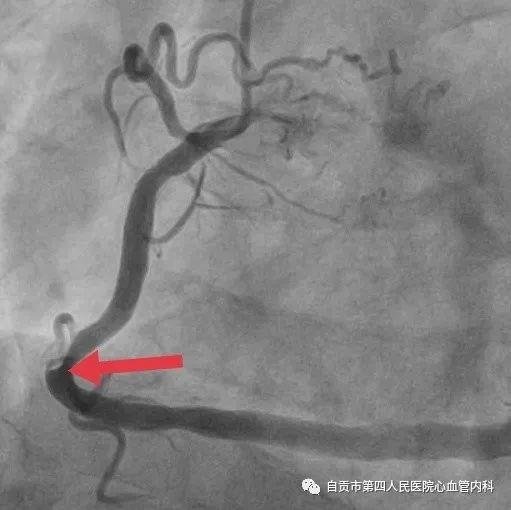

作者:汤勇 自贡市第四人民医院心血管内科引进又一利器“冠脉内超声检查(IVUS)”,助力冠心病精准治疗,目前我国冠心病发病率呈现一个高发的态势,冠心病的发病年龄也呈年轻化的趋势,20-30岁的人群发生急性心肌梗死也不少见。 ![]() 冠脉完全闭塞导致心梗 ![]() 急诊手术成功开通血管 药物加冠脉支架治疗是治疗冠心病的常规治疗手段,我们通常选择冠脉造影对患者的冠状动脉血管检查,由于冠脉造影显示的血管图像是二维图像,并不能完全真实地反映患者冠脉病变的实际情况,有可能造成不必要的支架植入,判断支架的大小完全依赖经验与造影图像,也有可能造成支架大小,长度选择不当。 ![]() ![]() 为了更精准对冠心病患者治疗,优化支架植入,减少支架植入的并发症的发生。 ![]() IVUS图像 ![]() 造影显示需要支架治疗 我院引进了美国波科公司的冠脉内超声检查(IVUS)检查设备,对患者的冠状动脉进行实时检查,为临床医生在对冠心病患者是否需要支架治疗,支架合理应用提供更为准确得信息。 ![]() 我们有一位患者在西昌某院因心肌梗死,行右冠状动脉支架治疗,当时冠脉造影检查提示右冠状动脉支架有一重度狭窄,建议择期再行支架治疗,患者慕名来我院来进一步检查。从冠脉造影的情况确实需要进行支架治疗,由于患者年轻,已安置支架4枚,故决定对患者进行冠脉内超声检查(IVUS)检查。 ![]() 支架局部膨胀不全 ![]() 冠脉内超声检查(IVUS) ![]() 支架直径恢复正常 患者冠脉内超声结果提示管腔面积能够满足心肌血供,且病变邻近血管直径大于5mm,不适合支架治疗。故建议其药物治疗,必要时复查造影。另外该患者造影显示已安置的支架显示膨胀不全的可能,进行冠脉内超声检查后显示支架内有明显膨胀不全的征象,故予以球囊扩张,支架管腔直径恢复正常。 在今后的冠心病治疗上,冠脉超声检查将发挥更大的作用,特别是复杂病变,左主干病变,钙化病变,闭塞病变方面,将大大减少冠脉介入治疗的并发症,再次支架治疗的发生率降低,将大大提高我院冠心病的精准治疗水平。 ![]() ![]() |